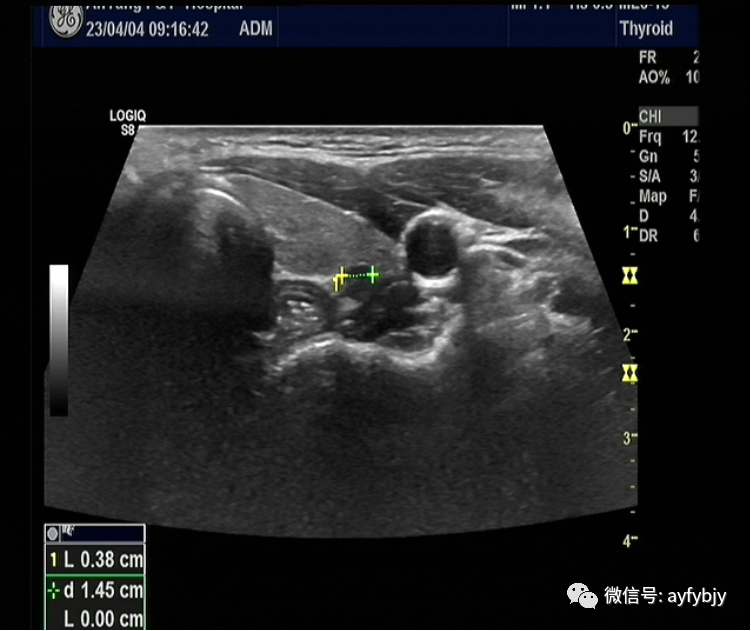

2023年4月4日9:00,22岁青年女性患者,因“体检发现左侧甲状腺结节1周”就诊于我院行进一步检查。行甲状腺彩超示:左叶下极近后背膜可探及约0.38cm×0.43cm×0.51cm低回声,形态欠规则,纵横比>1,边界尚清,内部回声均匀,后方回声正常,未见明显异常血流信号。双叶多发无回声。(左侧 C-TI-RADS  4a,右侧 C-TI-RADS  2类)。

待查无穿刺禁忌症后,于2023年4月4日16:00在超声引导下行甲状腺结节穿刺活检,精准取得了标本组织,并送检。操作过程时间仅仅为5分钟。穿刺全过程顺利,无不适。